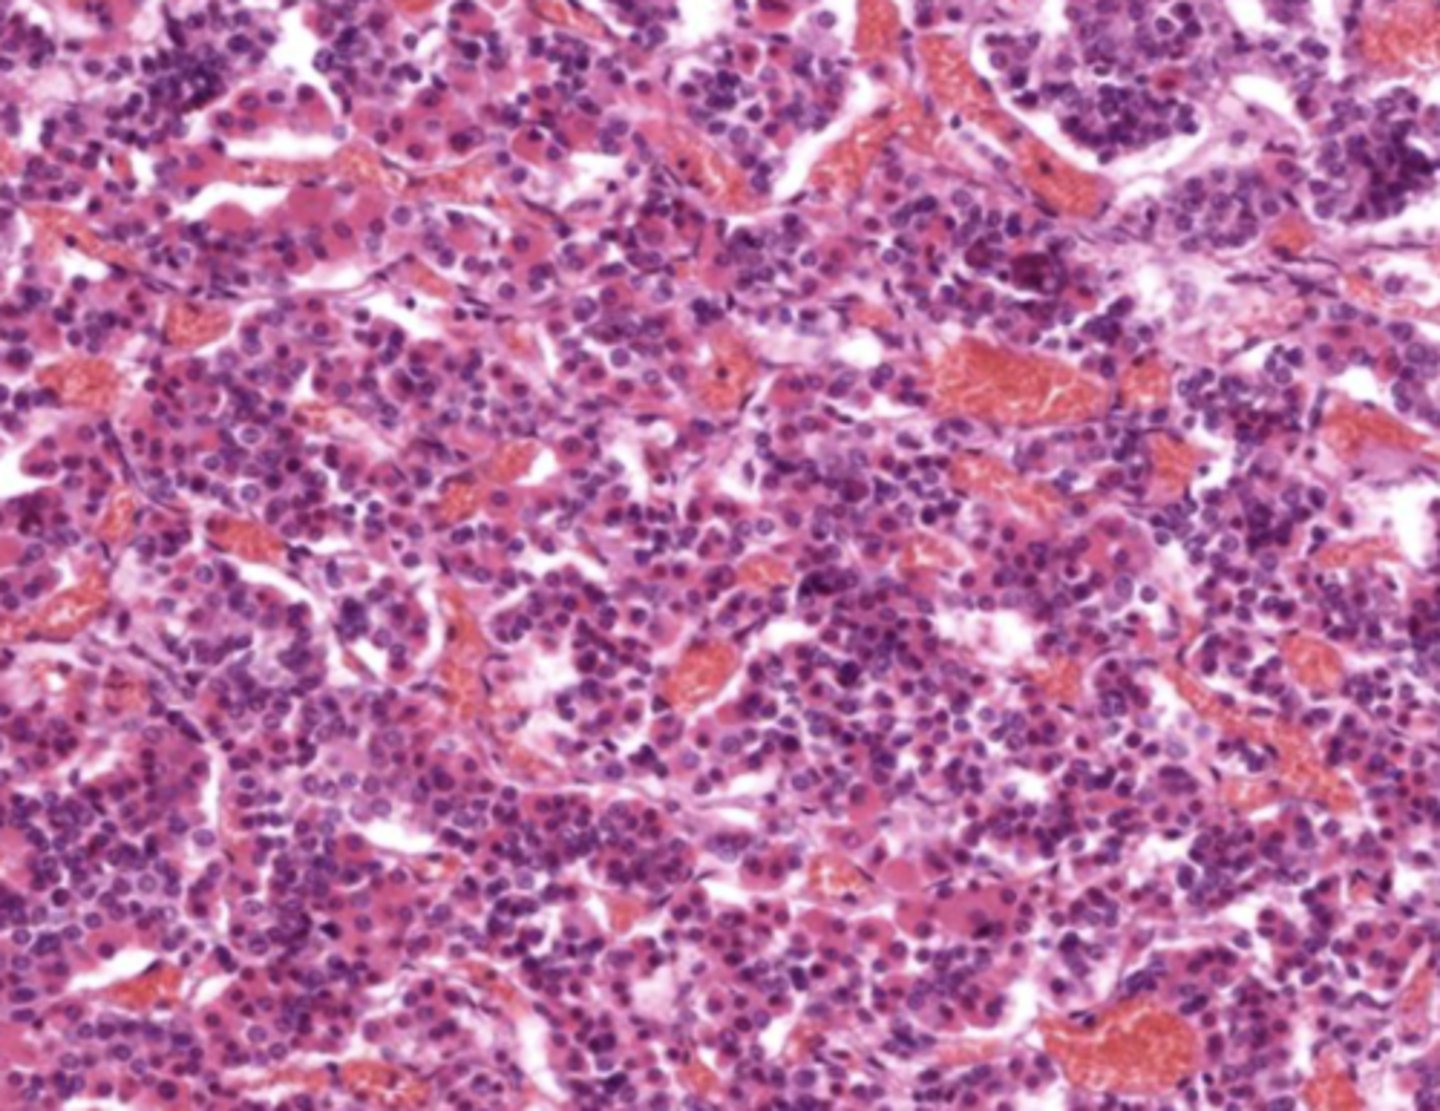

Thymus

Pancreas

Pancreatic islet

Adrenal gland

Adrenal cortex

Zona glomerulosa

Zona fasciculata

Zona reticularis

Adrenal medulla